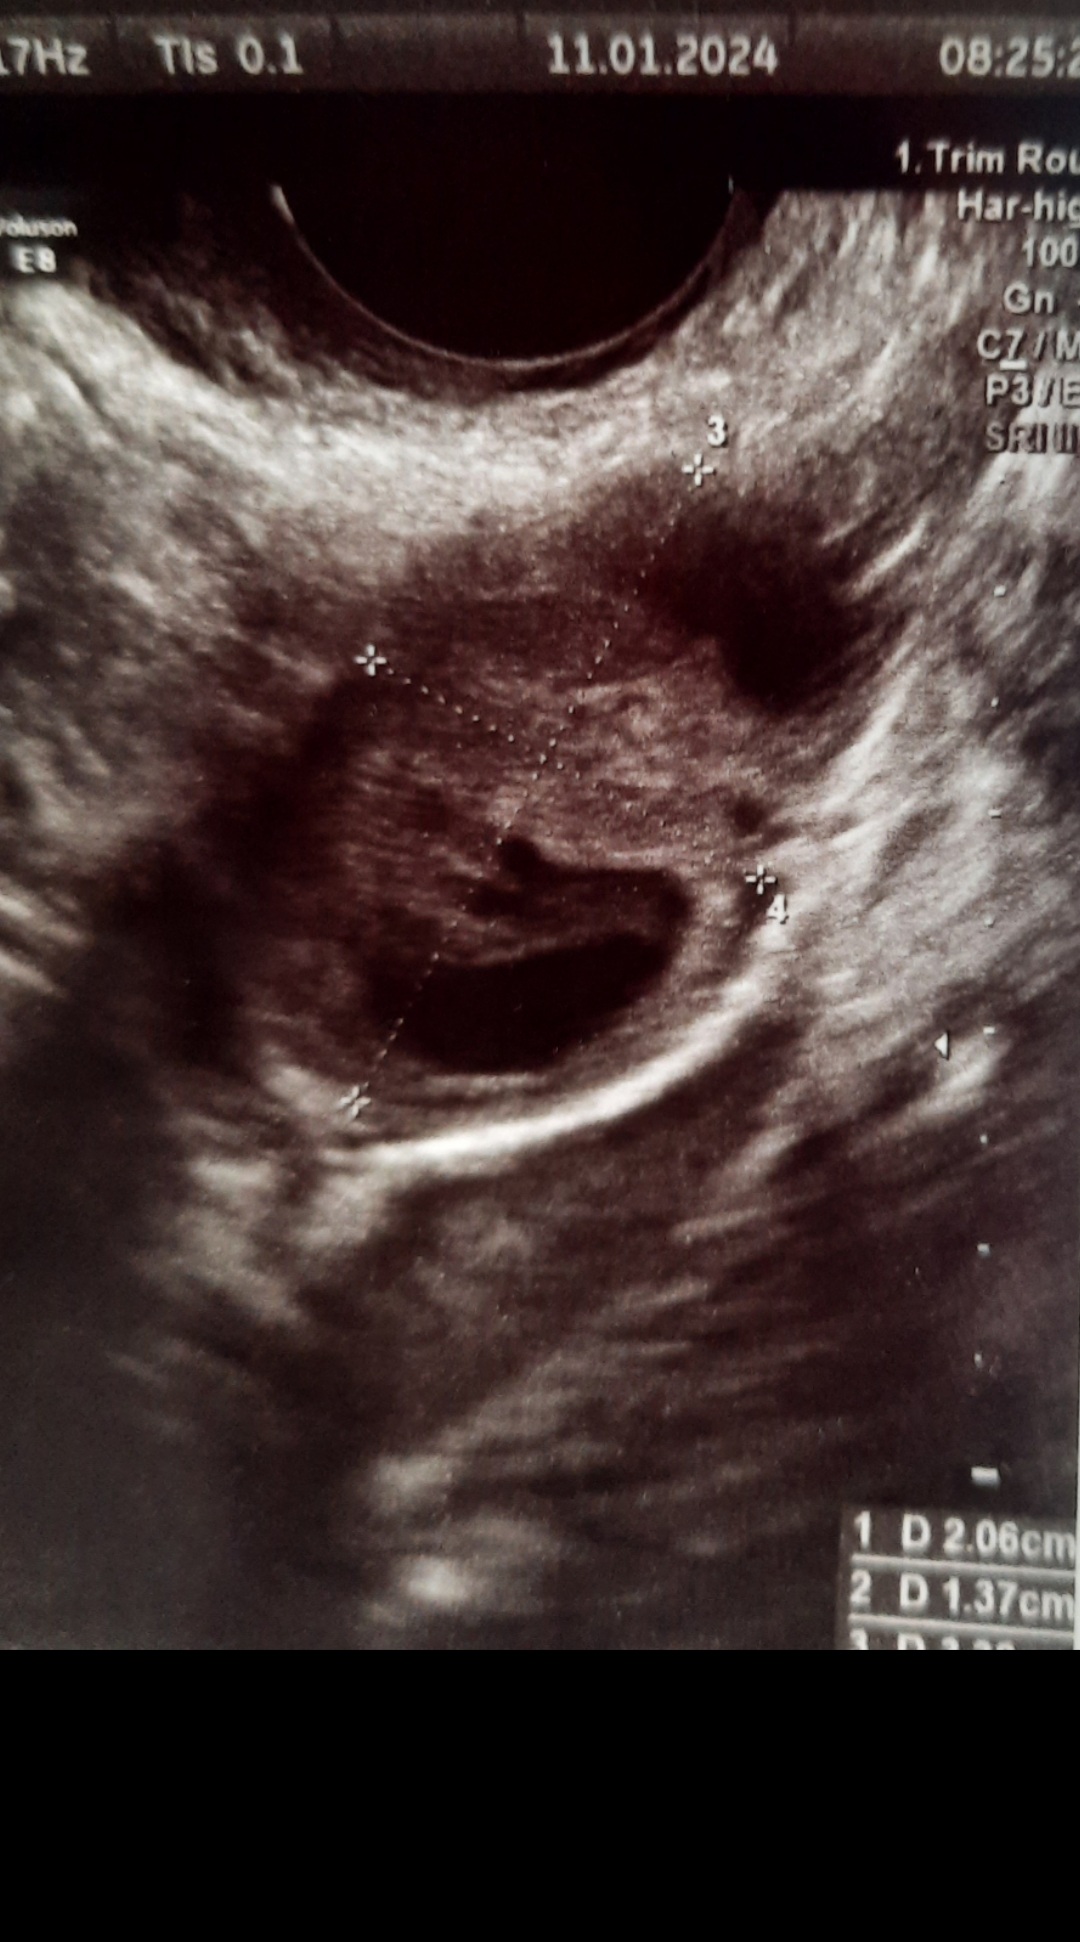

Czesc dziewczyny. Czy któraś może mogłaby mi powiedzieć czy też widzi na tym zdjęciu dwa pecherzyki czy mi się wydaje ?

Nie jestem lekarzem, ale gdybym miała oceniać, to jest to jeden pęcherzyk.Czesc dziewczyny. Czy któraś może mogłaby mi powiedzieć czy też widzi na tym zdjęciu dwa pecherzyki czy mi się wydaje ?

1 D 2.06cmA opis USG? W prawym dolnym rogu masz podane wielkości, sprawdź co jest wpisane na tą wielkość.